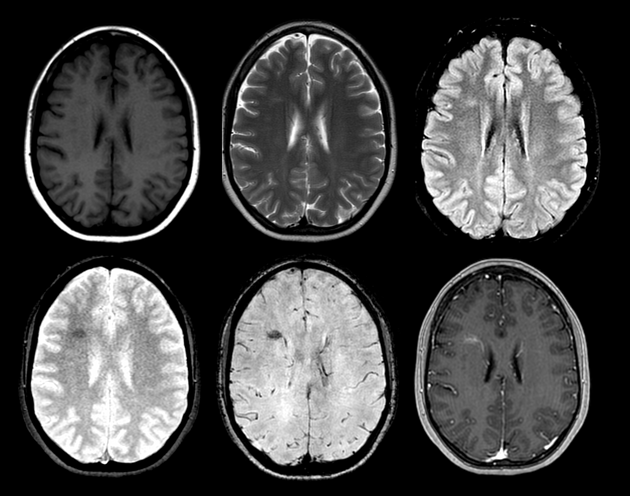

脑干毛细血管扩张症,SWI 低信号,结节样强化,强化程度要小于静脉

脑干较大毛细血管扩张症,T2WI 呈高信号,SWI 呈低信号,增强呈片状稍淡强化,可见引流静脉

右侧尾状核头毛细血管扩张症,平扫看不到,增强呈结节样强化,无水肿,矢状位和冠状位仔细观察结节内可见静脉向室管膜下引流

右侧海马旁回毛细血管扩张症,平扫显示不清,增强呈毛刷状,可见引流静脉

右侧放射冠相对较大的毛细血管扩张症,T2WI 和 FLAIR 呈高信号,SWI 呈低信号,增强呈片状稍淡样强化,可见引流静脉至室管膜下